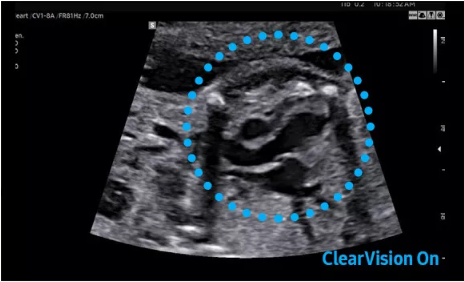

2D成像方面,Hera i10集成了包括ShadowHDR?、HQ-Vision?、ClearVision等多項具有三星“血統(tǒng)”的技術(shù),加強(qiáng)了圖像的陰影抑制、減少偽影、緩和模糊區(qū)。